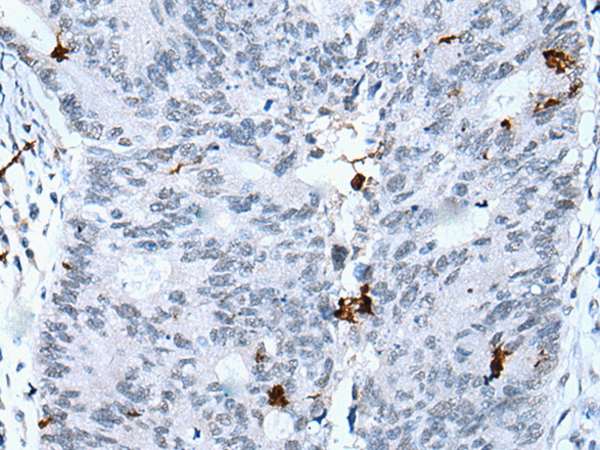

分类: 科研抗体货号: P05789别名: HOX1; HOX1E应用: IHC反应种属: Human, Mouse